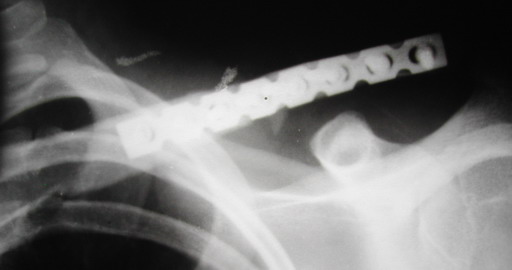

В приложении проект наших тезисов на съезд и клинический пример: Пациентка 23 лет поле неэффективного оперативного лечения (4 нед.) перелома ключицы спицей (была оперирована в С-Петербурге)(снимок после удаления спицы) и результат закрытого БИОС..

Один из вариантов, что удалось быстро найти, позже еще найду, но схема примерно такая (первое

вложение).

Мужик кочегар, срок нетрудоспособности 7 недель. Наружную конструкцию сняли через 3 недели. Далее без иммобилизации. Погруженную спицу можно убрать и через несколько месяцев, если жить не мешает.

Раньше не погружали, на рентгенограммах и натуре видно (последние 2 вложения). Как вариант спицы в периферическом отломке могут крепится на трехдырочную приставку, что дает возможность компрессии.